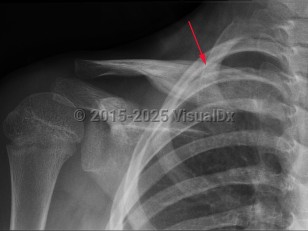

Chronic recurrent multifocal osteomyelitis (CRMO) is a rare nonbacterial cause of osteomyelitis. It is an autoimmune inflammatory disorder that causes multi-site, relapsing bone inflammation in the absence of typical infectious causes. Patients present with bone pain, swelling, and decreased mobility. CRMO most often occurs in children. CRMO sometimes co-exists with other autoimmune diseases such as inflammatory bowel disease or within a genetic syndrome. Nonsteroidal anti-inflammatory drugs (NSAIDs), corticosteroids, and bisphosphonates have all been used to treat CRMO. The disease typically has a relapsing and remitting course.

CRMO is now viewed by many as part of the spectrum of SAPHO syndrome.